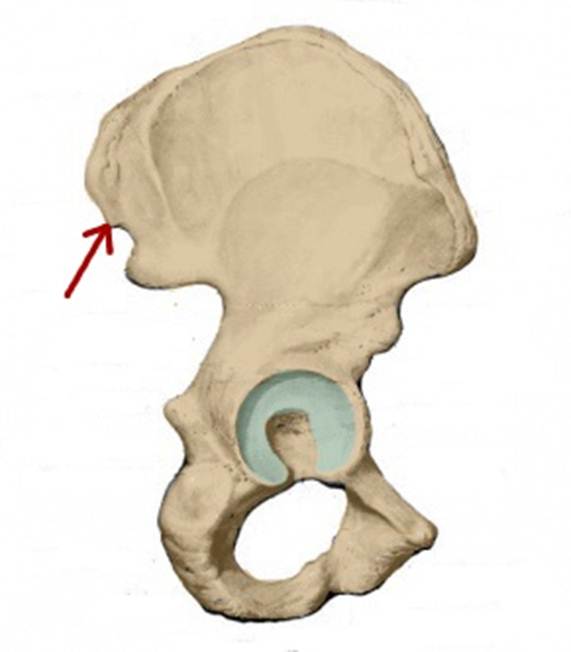

I:

S: Стрелка указывает на os pubis (латинский язык).

I:

S: Стрелка указывает на os ilium (латинский язык).

I:

S: Стрелка указывает на os ischii (латинский язык).

S: Стрелка указывает на ramus superior ossis pubis

S: Стрелка указывает на ramus inferior ossis pubis

S: Стрелка указывает на ramus ossis ischii

S: Стрелка указывает на foramen obturatum (латинский язык).

S: Стрелка указывает на tuberculum pubicum

S: Стрелка указывает на spina iliaca anterior inferior

S: Стрелка указывает на spina iliaca anterior superior

S: Стрелка указывает на eminentia iliopubica

I:S: Стрелка указывает на spina iliaca anterior superior